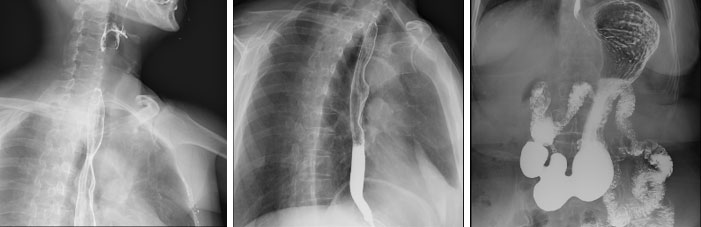

多种临床应用选择

SONIALVISION C200配置多种高级临床功能:可拓展设备的使用范围,完成多种特殊检测需求。